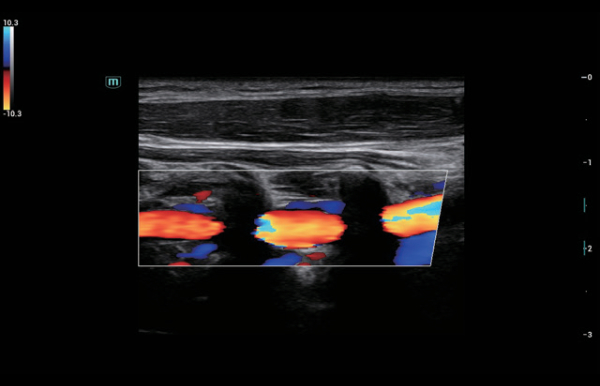

Solu??es abrangentes de imagens com tecnologia ZST+

A plataforma ZST+ ÃĐ uma inova??o extraordinÃĄria, representando a evolu??o do ultrassom. Transformando as mÃĐtricas de ultrassom: da forma??o convencional do feixe ao processamento baseado em dados de canais. Supera a limita??o de compensa??o tradicional entre resolu??o espacial, resolu??o temporal e uniformidade de tecido, oferecendo qualidade de imagem excepcional para solu??es de imagem infinitas com melhorias inigualÃĄveis.